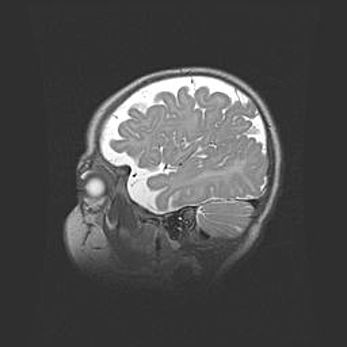

Церебральная ишемия II.

Возраст: 5 дней

Вес: 3400 г

Пол: женский

Окружность головы: 35 см

Срок гестации: 39 недель

Церебральная ишемия – это заболевание, характеризующееся недостаточностью (гипоксией) либо полным прекращением (аноксией) снабжения мозга кислородом по причине закупорки одного или нескольких сосудов. Это приводит к  что метаболическим расстройствам различной степени тяжести в тканях головного мозга, развитию коагуляционных некрозов и гибели нейронов.